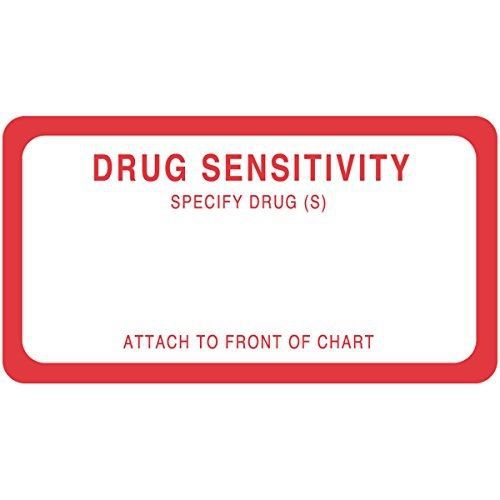

PDC Healthcare 59704577 Label Paper, Permanent, Drug Sensitivity, 3" x 1 5/8",